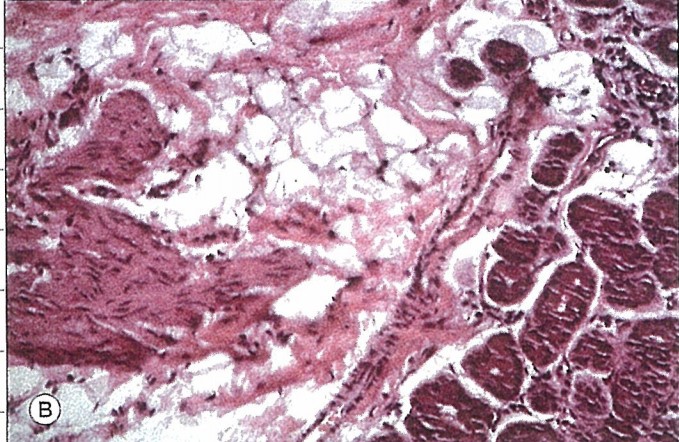

조직검사를 하엿을때 조직검사에서 횡문근 smooth muscle fiber 을 발견하는 경우,

병변이 눈물샘의 이소성 눈꺼풀엽이라는것을 시사합니다.

병변은 선명한 붉은색이고, 투명한 결정이 관찰되고 혈관화가 잘되어 있습니다.